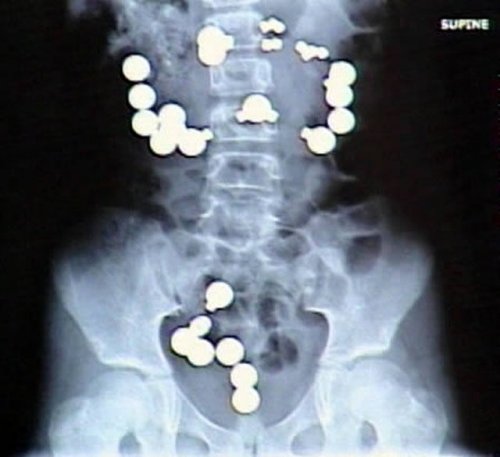

8-летняя Хейли Лентс (Haley Lents) из Индианы проглотила 10 магнитов и 20 стальных шариков из набора игрушек Магнетикс (Magnetix). Магниты и шары притянулись друг к другу в её пищеварительном тракте, сделав восемь дырок в кишечнике, из-за чего родителям пришлось отвезти девочку в больницу для срочной операции. Лентс позже рассказала журналистам, что магниты и стальные шарики «выглядели как конфеты».